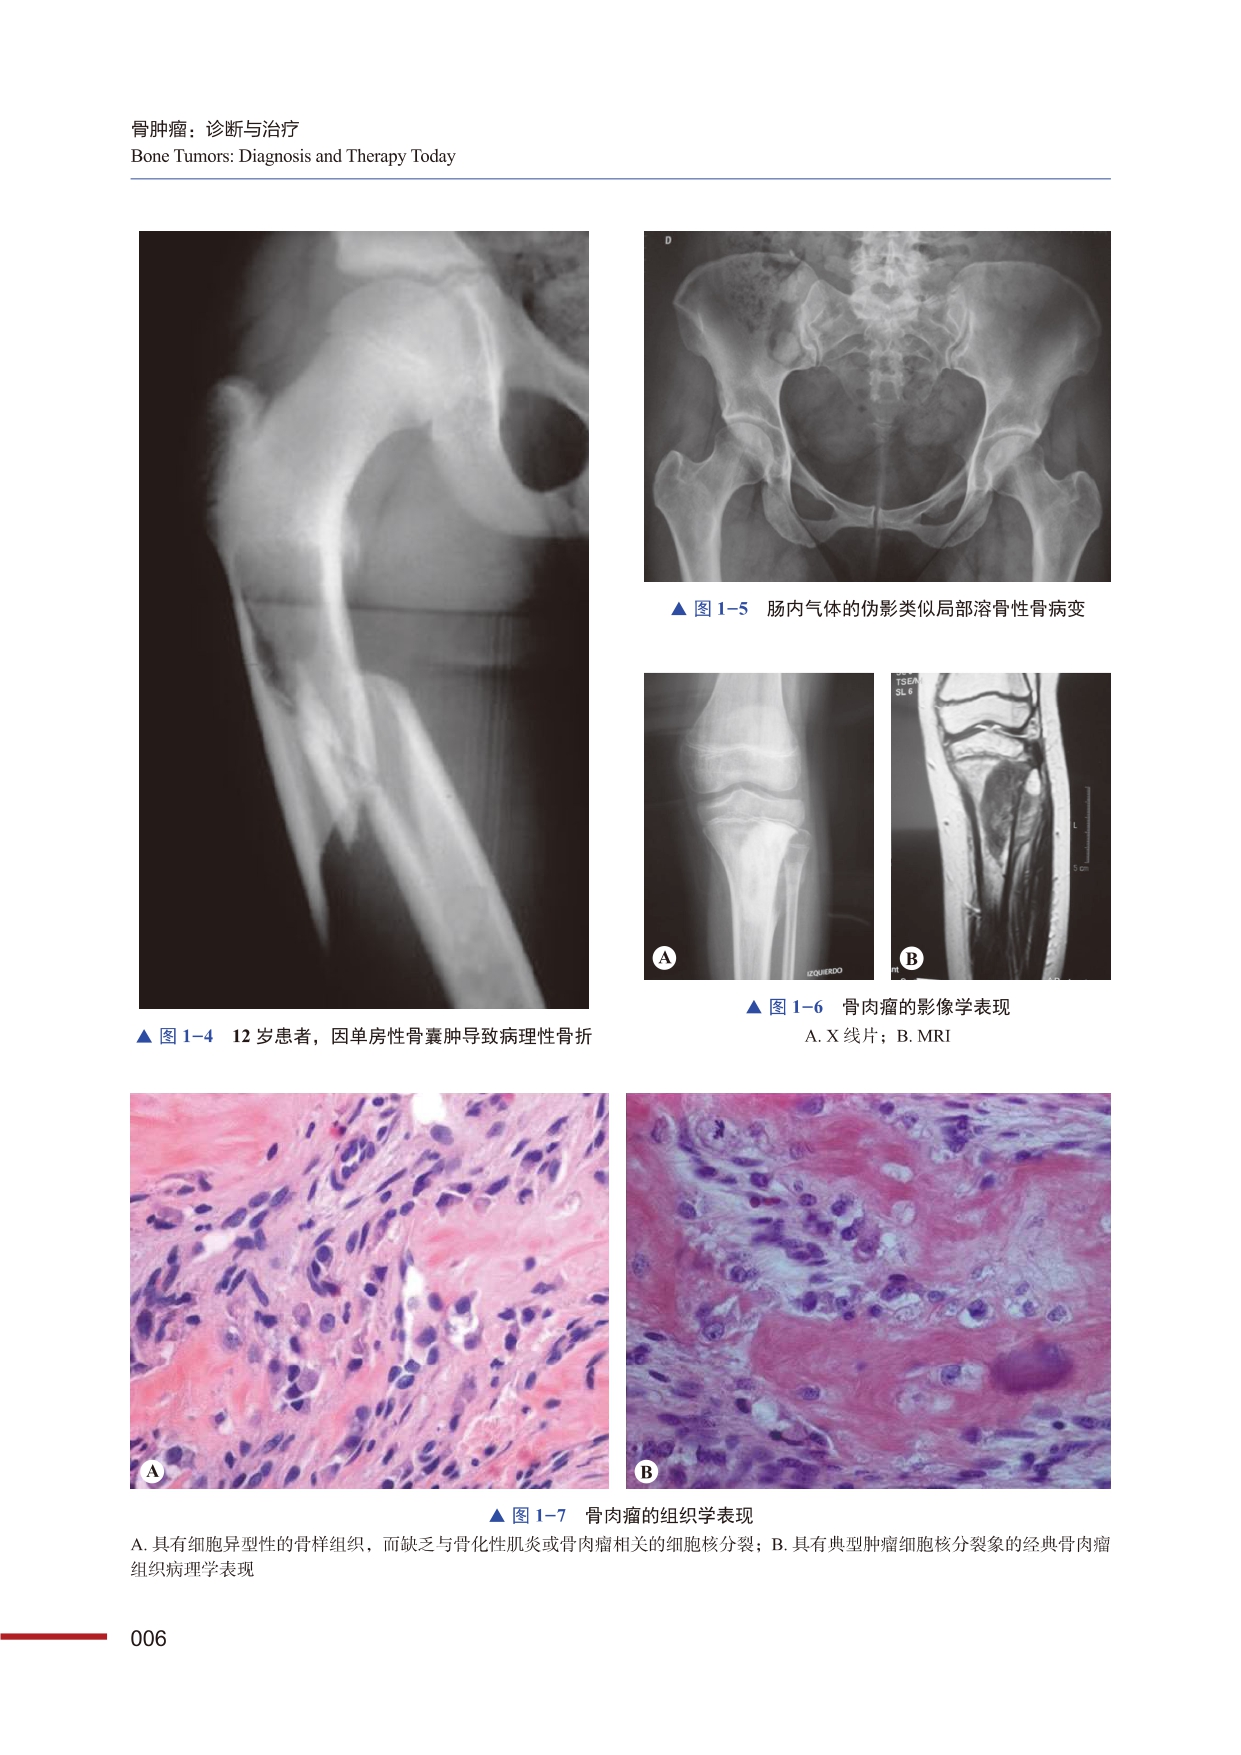

本书是一部全面系统介绍骨肿瘤诊断与治疗的实用专著。著者根据组织学来源对骨肿瘤病变进行了分类,对成骨性骨肿瘤、成软骨性骨肿瘤、血管来源骨肿瘤、结缔组织骨肿瘤等30余种骨肿瘤病变的流行病学、影像学、病理学、肿瘤外科学进行了全面系统的讲解,还对疾病的流行病学筛查、诊断鉴别、预后评估、治疗策略、康复随访等展开了详细论述。本书内容实用,阐释系统,对骨科及肿瘤科医生有较高的指导价值,也可为其他学科的年轻医生提供参考。